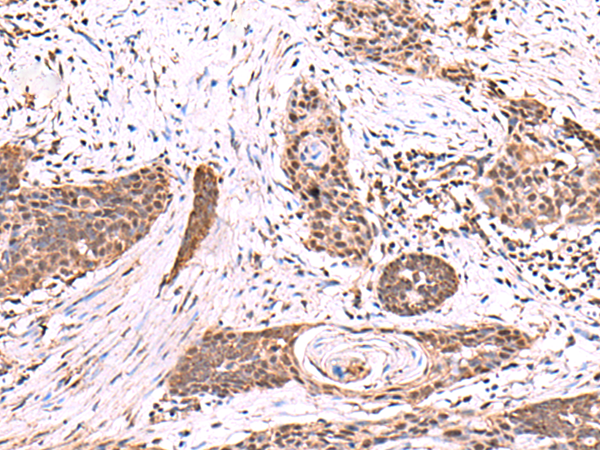

IHC positive control:

Human tonsil and Human esophagus cancer